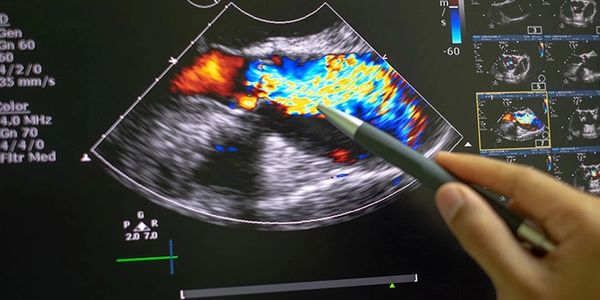

El ultrasonido es un examen médico no invasivo que ayuda a los médicos a diagnosticar y tratar condiciones médicas. Es seguro e indoloro. Produce imágenes del interior del organismo usando ondas de sonido. A las imágenes por ultrasonido también se las conoce como ecogra Utiliza una pequeña sonda denominada transductor y un gel que se coloca directamente sobre la piel.